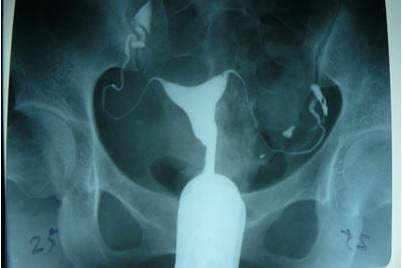

输卵管造影是用来检查女性输卵管通畅与否的一种检测方法。目前,输卵管造影是临床上应用较为广泛的方法之一。造影是通过导管经阴道、宫颈、子宫腔直接插向子宫角的输卵管开口处,对着输卵管推注造影剂而使输卵管显影,进而了解输卵管是否通畅、阻塞部位及宫腔形态的一种检查方法。

推注造影剂力,造影剂进入盆腔缓慢,在停注造影剂数十分钟后,可见造影剂在盆腔内弥散,但弥散欠佳。

输卵管完全不显影或显影一段后不再显影,且造影剂注入到一定剂量时阻力加大,盆腔内无造影剂影弥散。

造影剂积聚在输卵管内,输卵管常扩张呈囊状或腊肠状,以远端明显,多伴有输卵管伞端阻塞。盆腔内一般无造影剂影弥散。